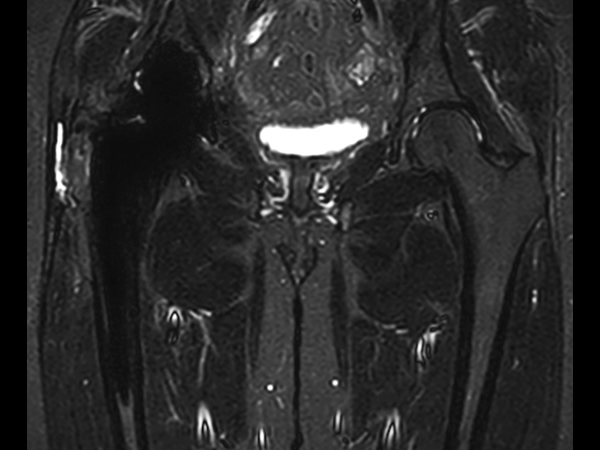

Hip imaging with metal implant

Used Solution

**Only for use with MR Safe or MR Conditional Implants by strictly following the Instructions for Use.